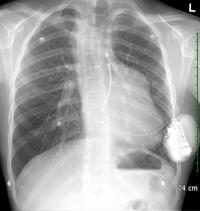

OTTAWA, October 3, 2012 – A new ground-breaking technology was recently used at the University of Ottawa Heart Institute (UOHI) where two cardiologists, Dr. David Birnie and Dr. Pablo Nery, implanted a new innovative leadless defibrillator, the subcutaneous implantable cardioverter defibrillator (S-ICD), to a 18 year-old patient. Under Health Canada's special access program, this was only the third time this new type of ICD had been implanted in Canada.

What makes the new device special is that it is entirely subcutaneous. No part of it actually touches the heart. Instead, an electrode is implanted just under the skin near the heart. The defibrillator is connected to the electrode, and monitors the heartbeat at all times. If needed, it delivers a shock to the heart muscle to restore its normal rhythm.

Another advantage is more aesthetic in nature but, nonetheless, important for young people. A conventional transvenous defibrillator sits on the front on the chest, just under the collarbone, and is easy to see. The S-ICD, in comparison, is implanted to the side, under the patient's arm, and with a much smaller incision than with the transvenous defibrillator. That, said Dr. Nery, is an important consideration for many patients in terms of body image and quality of life.